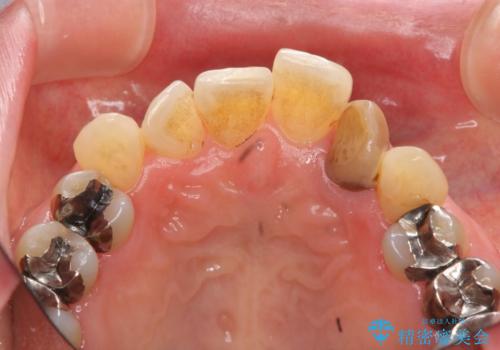

自然な色調のクラウンが製作され、審美障害が改善し喜んでいただくことができました。

- 15.4万円(ジルコニアクラウン・仮歯・ファイバーコア)費用は治療当時の料金となります